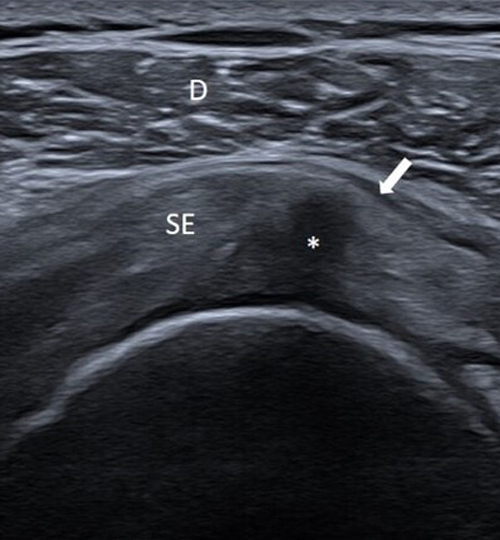

L’échographie est un examen simple, rapide et non invasif qui permet d’évaluer de nombreuses structures articulaires et tendineuses et de guider des gestes infiltratifs. Cependant, cette technique a certaines limites et les résultats doivent être interprétés dans le contexte clinique. L’essentiel pour le MG.